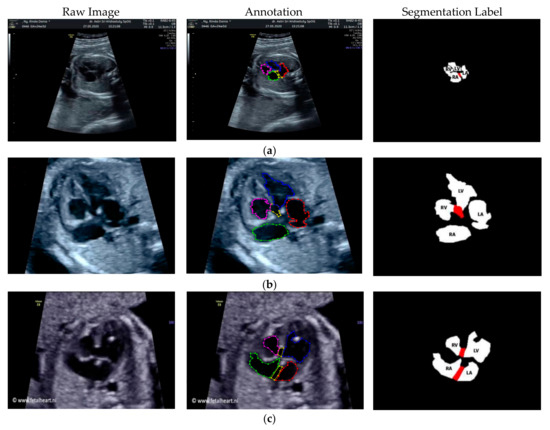

Especially for heart defect detection, only 4CH view was used to analyze ASD, VSD, and AVSD images. Annotated images indicate the position of defect in the atrium, ventricle, or both of them. Figure 4 depicts the sample of annotated images for a standard view of 4CH, 3VT, LVOT, and RVOT, and Figure 5 shows the sample annotated images of defect position in ASD, VSD, and AVSD. Finally, the whole annotated images are labelled as the ground truth database, and it was saved in the JSON file format (json).

Figure 4.

The sample of annotated images by maternal–fetal clinician for standard fetal heart view segmentation in (a) 4CH (orange: view, cyan: AoA, red: LA, grey: RA, green: LV, and red: RV); (b) LVOT (orange: view, cyan: LA, purple: RV, and blue: LV); (c) RVOT (orange: view, green: MPA, red: DUCT, and yellow: SVC); and (d) 3VT (purple: view, yellow: AoA, green: SVC, and red: DUCT); based on normal anatomy.

Figure 5.

The sample of annotated image by maternal–fetal clinician for heart defect detection in case: (a) ASD; (b) VSD; and (c) AVSD. In the annotation, the green line is RA, the red line is LA, the purple line is RV, the blue line is LV, and the yellow line is defect.